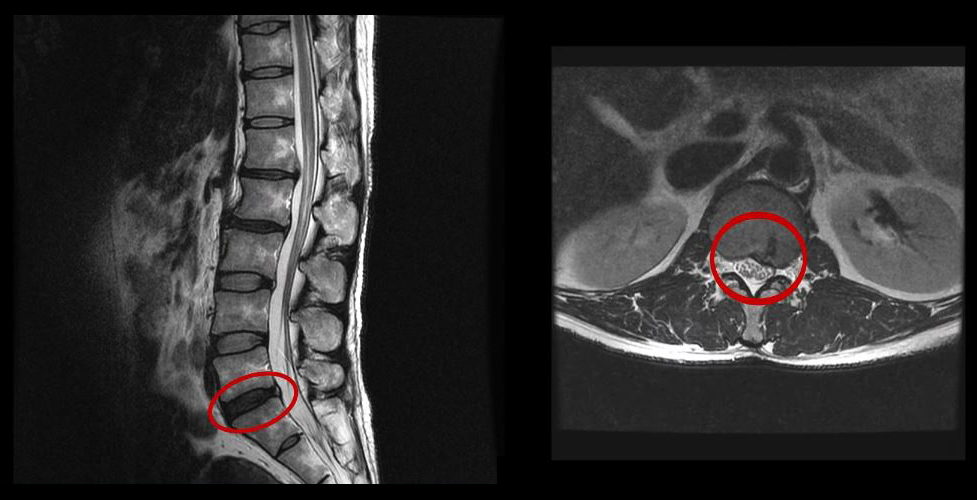

그런데 이 환자분의 MRI를 보면 여러 마디에 퇴행성디스크가 있습니다.

이 환자분은 MRI상으로 거의 대부분 마디의 디스크가 퇴행되고 수핵이 밀려나와 있으며, 정상적인 허리 마디는 4-5번 하나 정도입니다. 그렇기 때문에 MRI만 보면 아마 대부분의 병원에서 허리디스크탈출 또는 퇴행성디스크로 인한 허리통증 및 다리통증으로 진단하고 치료할 것입니다. 이분도 그래서 20년간 그런 치료를 무수히 많이 받았으나 그 어떤 치료도 별 도움이 되지 않았습니다.

이 환자분처럼 오랜 기간 만성적인 허리통증이 있고, 엉덩이가 저리면서 심지어는 양쪽 다리저림까지 있는 환자분들이 많습니다. 그런데 이 환자분의 MRI를 보면 여러 마디의 퇴행성디스크, 디스크탈출, 황색인대의 두꺼워짐, 후관절의 퇴행 등 다양한 병변들을 가지고 있는 걸 볼 수 있는데요. 그렇기 때문에 많은 병원에서 이분을 디스크로 진단하고 거기에 따른 치료가 이루어졌습니다. 그러나 저희가 보기에는 이분의 MRI상으로 보이는 여러 마디의 디스크 문제가 이 환자분이 갖고 있는 증상을 설명할 수 없었습니다.